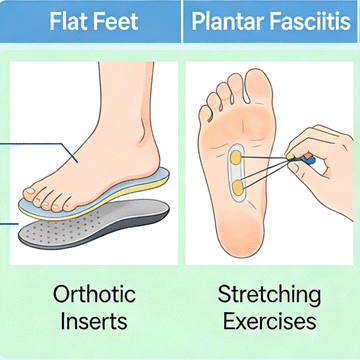

Zhengzhou Zhenshan Medical Equipment Co., Ltd. was formally established in 2017. The company specializes in R&D, production and sales of rehabilitation aids and consumables, including orthoses, low-temperature thermoplastic sheets and orthopedic insoles. The company has a strong R&D team, a professional marketing team and a perfect after-sales service system. The products are mainly exported to Europe, Southeast Asia, the Middle East, Africa and many other countries."People-oriented, scientific spirit, win-win cooperation, continuous learning" is our company's corporate values. We will do our best to serve every customer, produce better products, and make due contributions to the medical device industry! We look forward to cooperating with you to create a brilliant future!